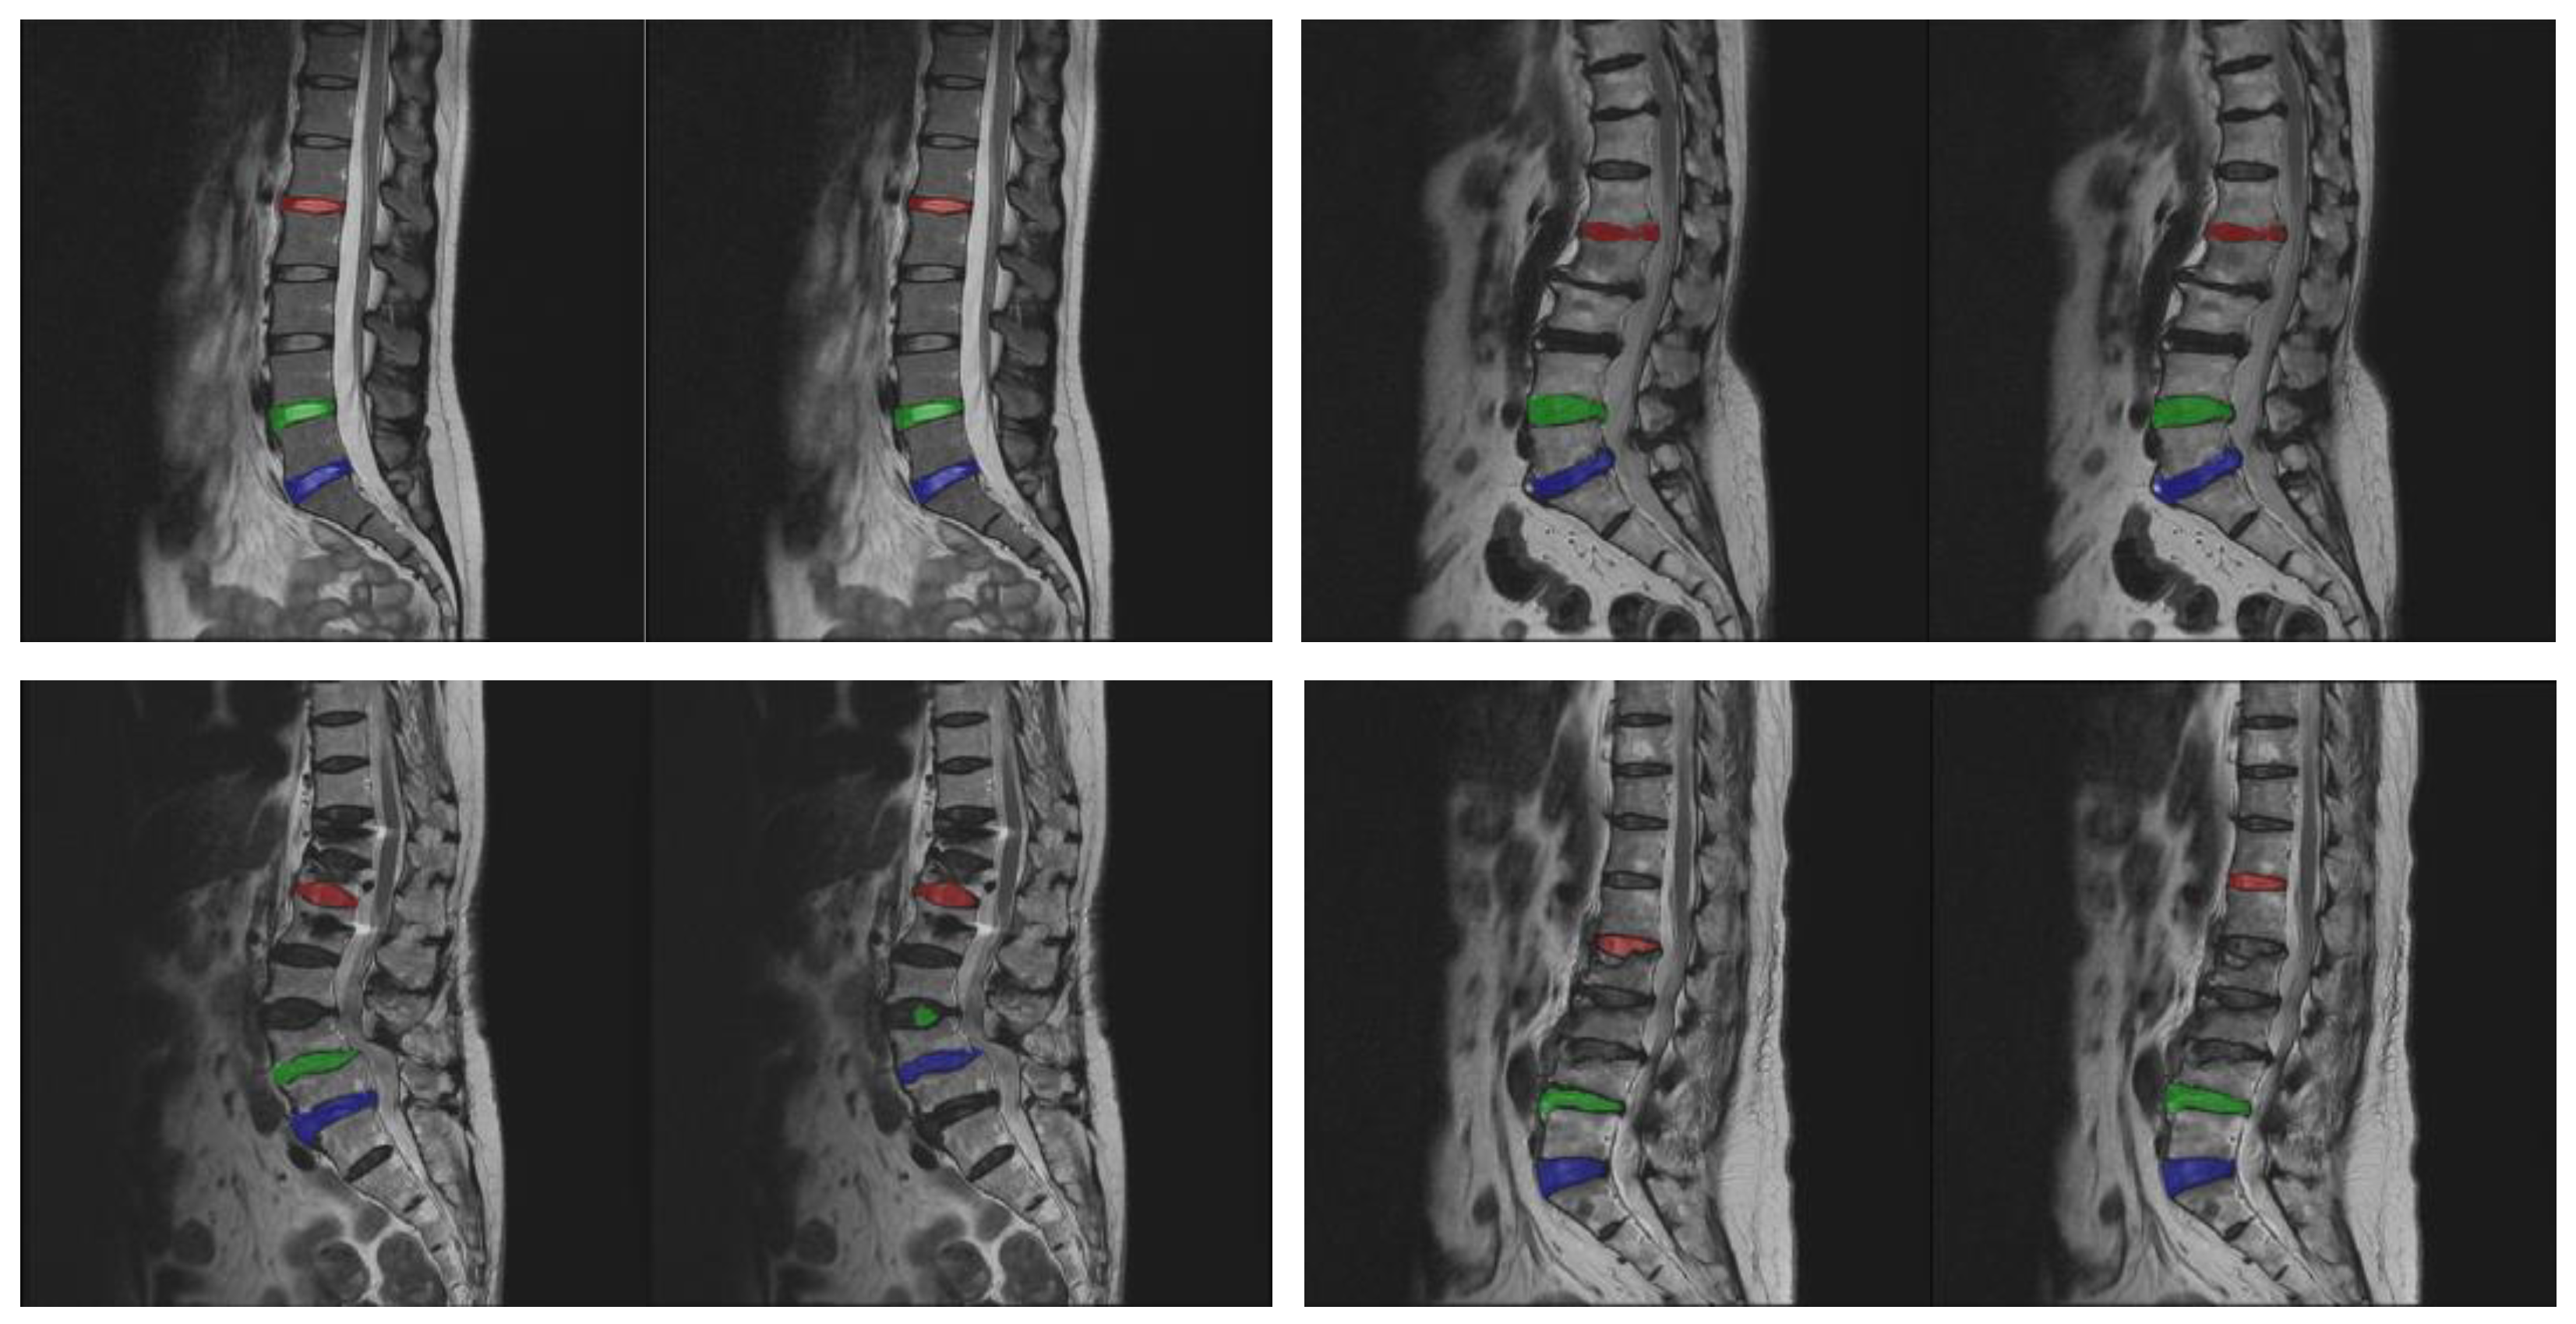

Table 3 shows the performance comparison of scanning and saliency map prediction algorithms for single-disc segmentation. The experimental steps are to perform the sub-image cropping method and the sub-image disc segmentation method on a single intervertebral disc and restore the result to the original image size. From the perspective of the number and accuracy of correctly predicted images, it is obvious that the saliency map prediction algorithm is better than the scanning algorithm. The L1/L2 intervertebral disc has lower values of the number and accuracy of correctly predicted images because this disc is very similar to its adjacent discs. Its segmentation is more challenging. The mean IoU is also roughly higher than 70%, except for the L1/L2 intervertebral disc. Figure 7 shows the correct and incorrect sampling images of a single intervertebral disc segmentation. Most of the segmentation errors occur when the wrong disc is found or the IoU value is lower than 0.7.

3.3. The Evaluation of Proposed Method

Figure 7. Correct versus incorrect sampling images of individual disc segmentation. The upper row represents correct segmentation, and the lower row represents incorrect segmentation. The left side of each pair of images is the standard mask, and the right side is the predicted result.